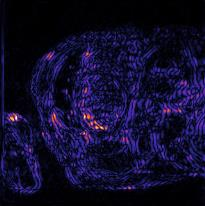

Recently, deep neural networks have greatly advanced undersampled Magnetic Resonance Image (MRI) reconstruction, wherein most studies follow the one-anatomy-one-network fashion, i.e., each expert network is trained and evaluated for a specific anatomy. Apart from inefficiency in training multiple independent models, such convention ignores the shared de-aliasing knowledge across various anatomies which can benefit each other. To explore the shared knowledge, one naive way is to combine all the data from various anatomies to train an all-round network. Unfortunately, despite the existence of the shared de-aliasing knowledge, we reveal that the exclusive knowledge across different anatomies can deteriorate specific reconstruction targets, yielding overall performance degradation. Observing this, in this study, we present a novel deep MRI reconstruction framework with both anatomy-shared and anatomy-specific parameterized learners, aiming to "seek common ground while reserving differences" across different anatomies.Particularly, the primary anatomy-shared learners are exposed to different anatomies to model flourishing shared knowledge, while the efficient anatomy-specific learners are trained with their target anatomy for exclusive knowledge. Four different implementations of anatomy-specific learners are presented and explored on the top of our framework in two MRI reconstruction networks. Comprehensive experiments on brain, knee and cardiac MRI datasets demonstrate that three of these learners are able to enhance reconstruction performance via multiple anatomy collaborative learning.